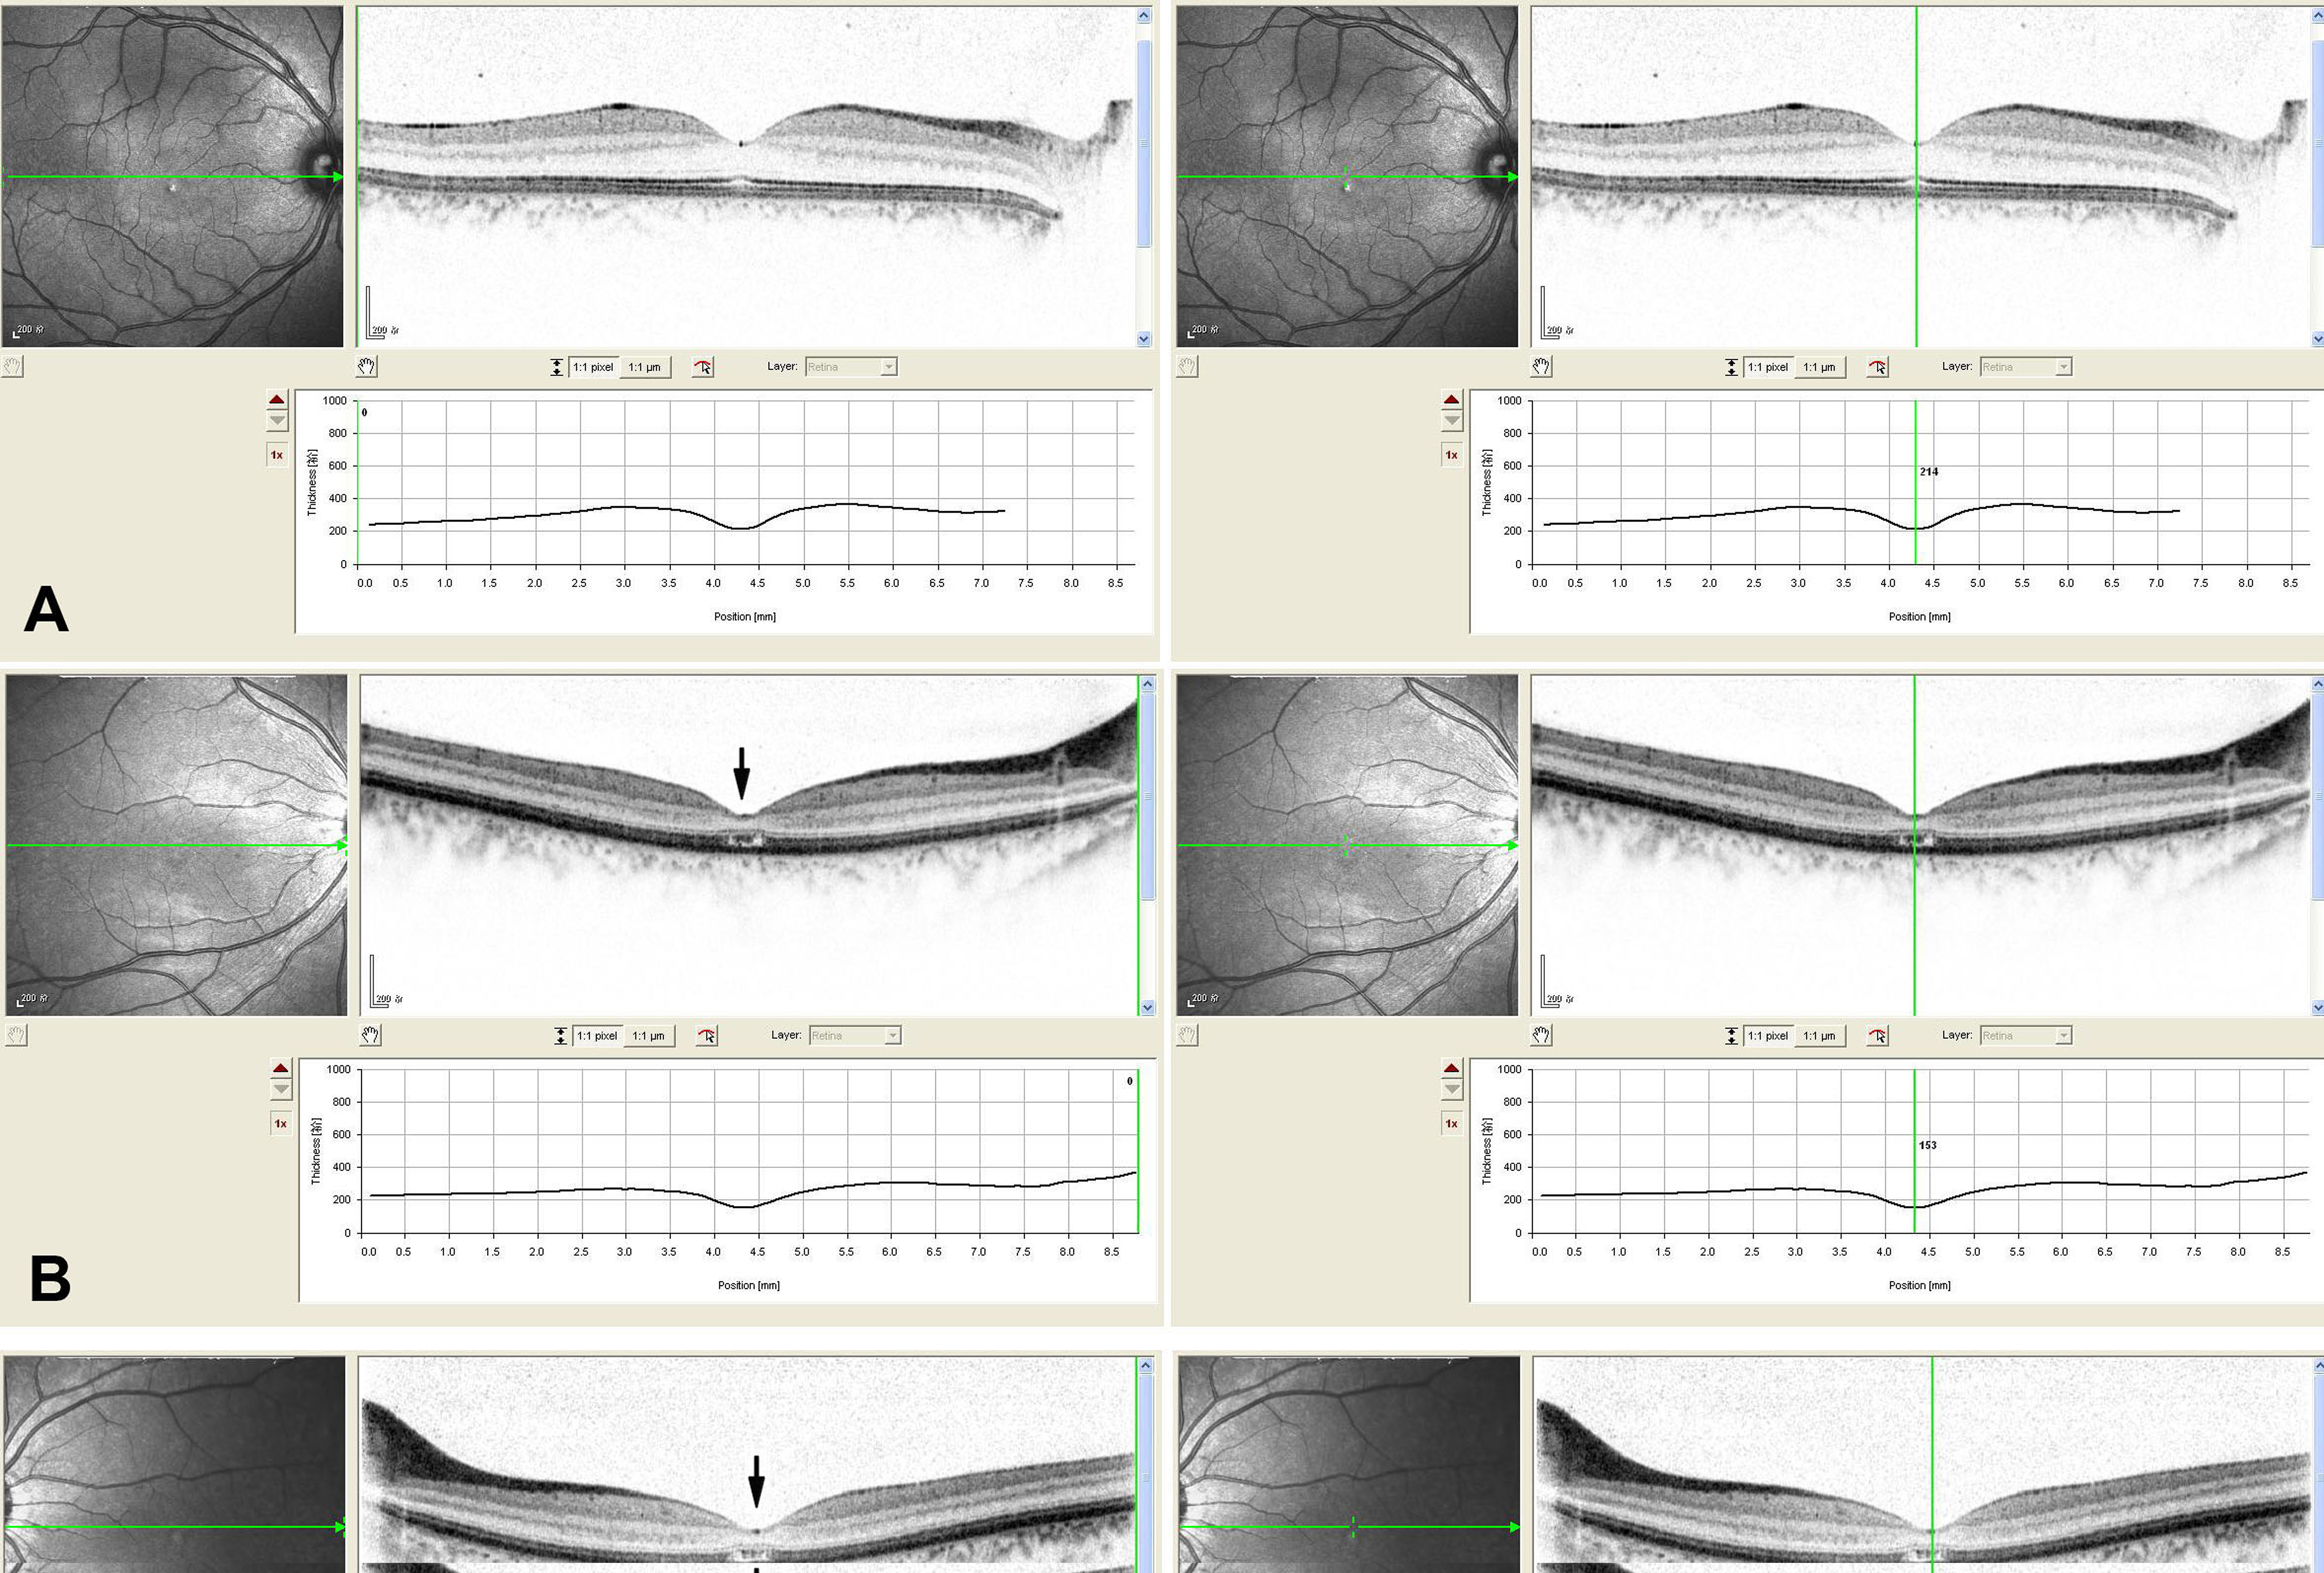

Figure 3. Macular optical coherence tomography images from a visually normal subject and the proband of this family with cone dystrophy.

A: The macular optical coherence tomography images of the right eye from a normal individual show organization of retinal microstructures

with a well defined photoreceptor inner/outer segment layer and normal thickness (214 μm). B and C: The macular optical coherence tomography images of both eyes from the proband exhibit loss of inner/outer segment layer

and thinning of the retina in the macular area (151 μm of the right eye, 153 μm of the left eye).